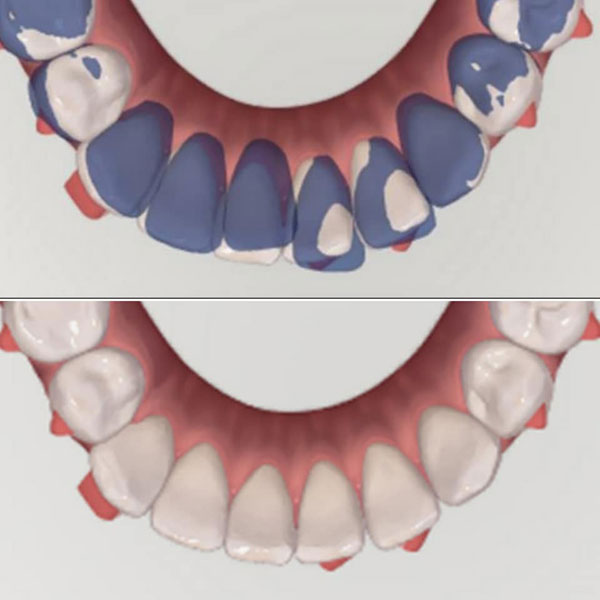

| The planned over-corrections in rotation and uprighting |